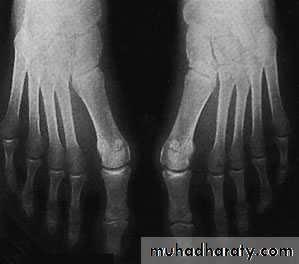

Hallux valgus:

It’s the commonest foot and musculoskletal deformity seen in practice.There is valgus deviation of the big toe with mild medial rotation where the nail facing slightly to the medial side, there is also overcrowding of the other toes with the 2nd. Toe usually develops the deformity known as hammer toe (extension of the metatarsophalangial joint, flexion of the proximal interphalangial and extension of the distal interphalangial joint).

Metatarsus primus varus: there is forefoot splaying with excessive primary varus position of the 1st. metatarsal bone that predispose for lateral deviation of the big toe during shoe wear.

X-ray:

Taken with the patient standing to show the degree of metatarsal and hallux angulations.Also it shows the state of the joint being normal, arthritic or subluxated.